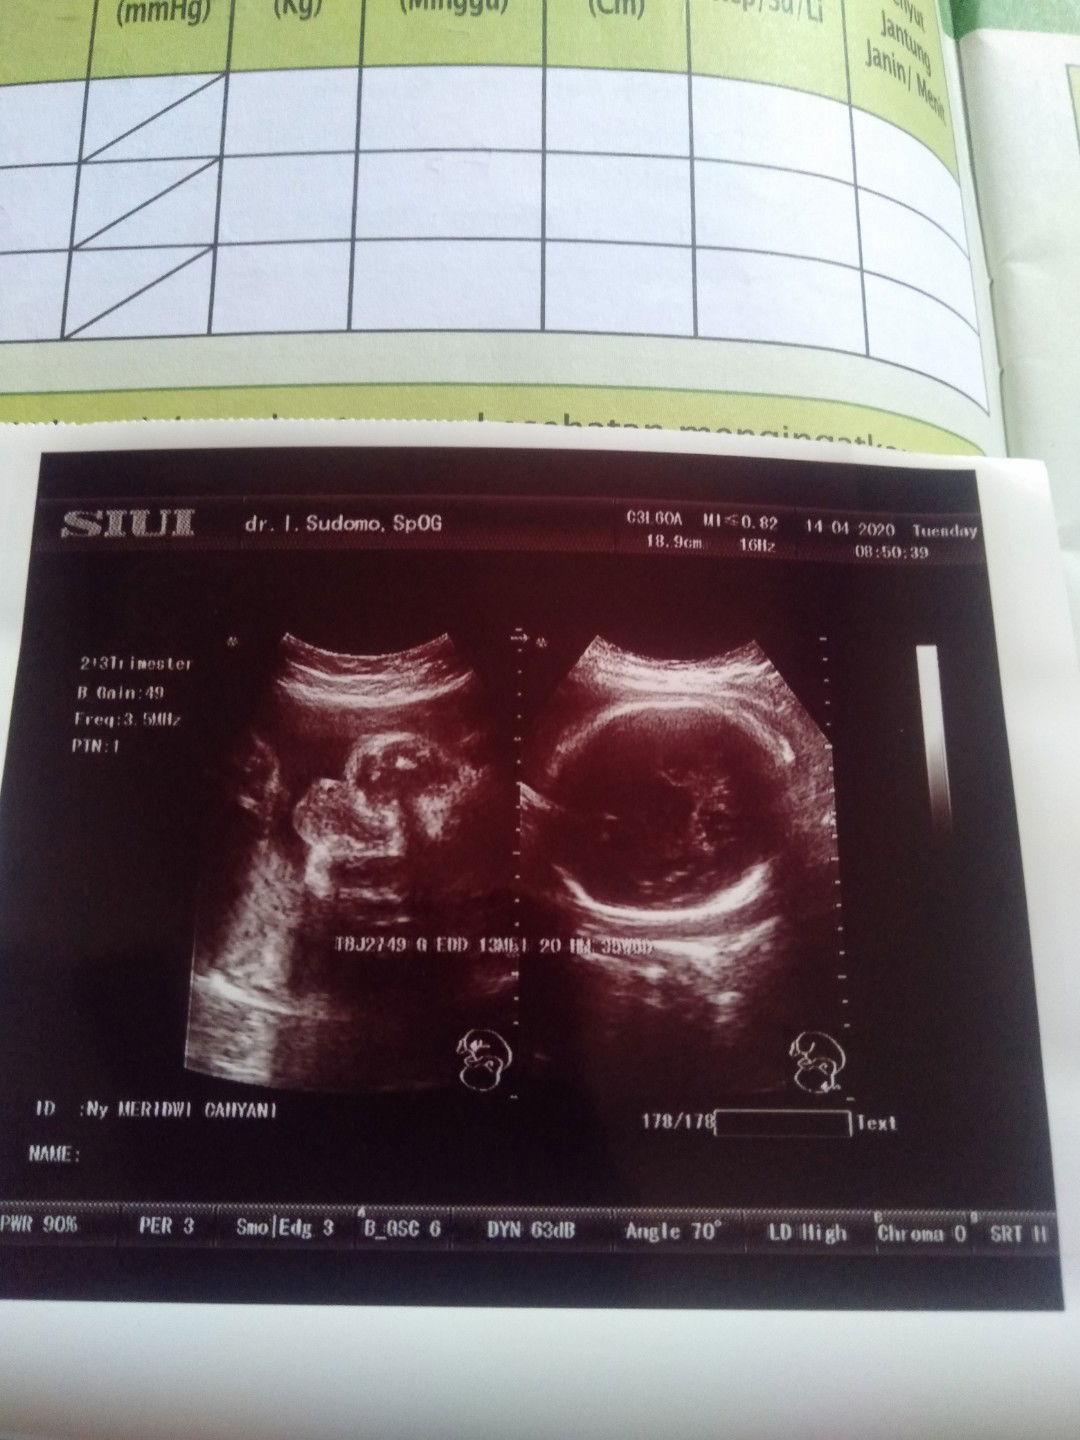

Kepleset Di kamar mandi